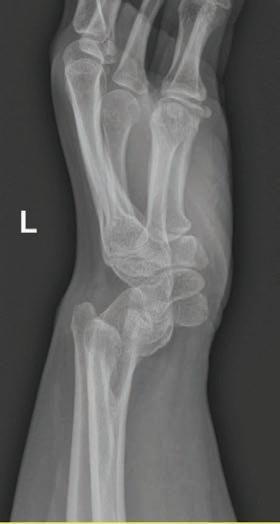

•Enfermedad rara de la placa de crecimiento radial en un adulto joven que responde a terapias ‘Deformidad de Madelung’: Informe de caso

Enfermedad rara de la placa de crecimiento radial en un adulto joven que responde a terapias ‘Deformidad de Madelung’: Informe de caso.....................................................................37

Colaboradores: